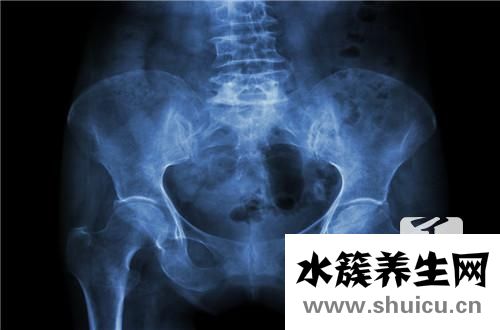

為了評估盆腔腫塊是好還是惡性,可以根據(jù)常規(guī)血液檢查中的白細胞計數(shù)來判斷。 任何患有骨盆腫塊的人都應該去正規(guī)醫(yī)院進行詳細檢查。 由于該疾病具有許多可變性,因此如果不進行詳細檢查,則人眼無法分辨出該疾病的某些特征。

盆腔包塊的血常規(guī)化驗可查驗白細胞計數(shù),10x109/L,以單核細胞上升主導。